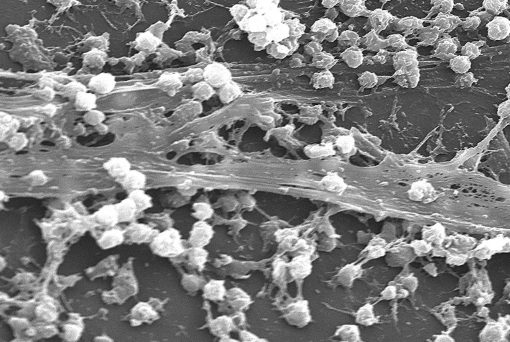

با توجه به پیشرفت تحقیقات و دانش در طول سالها، بیوفیلمها – باکتریایی و قارچی – در انواع شرایط سلامت نقش دارند. در فراخوانی در سال 2002، مؤسسه ملی بهداشت (NIH)، اشاره کرد که بیوفیلمها “بیش از 80 درصد از عفونتهای میکروبی در بدن” را تشکیل میدهند.

بیوفیلمها میتوانند روی وسایل پزشکی خاص مانند دریچههای مصنوعی قلب، پروتزهای مفصلی، کاتترها و ضربانسازها رشد کنند. این به نوبه خود منجر به عفونت میشود. این پدیده اولین بار در دهه 1980 زمانی که بیوفیلمهای باکتریایی روی کاتترها و ضربانسازهای داخل وریدی یافت شد، مورد توجه قرار گرفت. با توجه به مقاله 2004 در Nature Reviews Microbiology، در میان سایر عفونتها، بیوفیلمهای باکتریایی باعث ایجاد اندوکاردیت عفونی و پنومونی در مبتلایان به فیبروزکیستیک میشوند.

A.C. Matin، پروفسور میکروبیولوژی و ایمونولوژی در استنفورد گفت: «دلیل اینکه تشکیل بیوفیلم باعث نگرانی بزرگی شده است این است که درون یک بیوفیلم، باکتریها در برابر آنتیبیوتیکها و ضدعفونیکنندههای دیگر که میتوانید برای کنترل آنها استفاده کنید، مقاومتر هستند».

در واقع، در مقایسه با باکتریهای شناور آزاد، باکتریهایی که بهعنوان یک بیوفیلم رشد میکنند میتوانند تا 1500 برابر، در مقابل آنتیبیوتیکها و سایر عوامل بیولوژیکی و شیمیایی مقاومتر باشند.

بیوفیلمهای قارچی نیز میتوانند با رشد روی دستگاههای جایگیری شده در بدن انسان، باعث عفونت شوند. طبق مقالهای که در سال 2014 در مجله Cold Spring Harbor Perspectives in Medicine منتشر شد، گونههای مخمر مانند اعضای جنس کاندیدا روی ایمپلنتهای سینه، ضربانسازها و دریچههای مصنوعی قلب رشد میکنند.